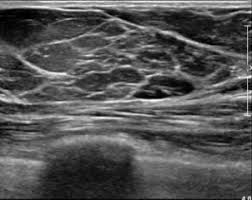

El ACUSON Maple Ultrasound System admite un espectro completo de aplicaciones de imagen de mama y de pequeñas partes, ayudando a nuestros especialistas a visualizar en tiempo real los detalles finos del tejido sin exposición a radiación.

Un dato interesante: las imágenes por ultrasonido (sonomamografía) pueden revelar cambios en los tejidos blandos antes de que sean visibles en la mamografía, lo que la convierte en una herramienta invaluable para el cuidado personalizado en etapas tempranas del cáncer.